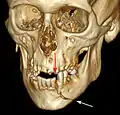

كسر الفك السفلي

كسر الفك السفلي (بالإنجليزية: Mandibular fracture) أو يعرف بأنه كسر الفك، هو كسر يحصل خلال عظام الفك.[1][2][3] يحدث هذا النوع من الكسور بسبب التعرض لإصابة وعادة ما تكون مصاحبة برضّة الوجه.

تتضمن أنواع كسر الفك السفلي الكسور في منطقة الارتفاق الذقني ورأد الفك وزاوية الفك وعنق اللقمة.